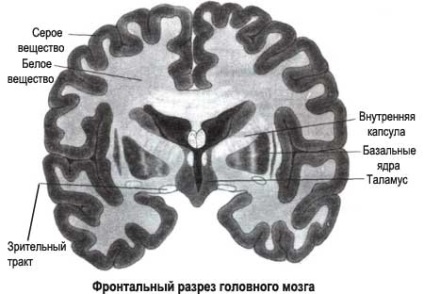

În funcție de locul schimbărilor structurale sunt două tipuri de patologie:

cut creier.

- leykoareoz periventricular;

- leykoareoz subcortical.

tip atrofie periventricular presupune localizarea leziunilor materiei albe sub forma unei benzi din jurul ventriculelor laterale ale creierului, sau sub formă de „domuri“ situate deasupra ventricule.

In leykoareoz subcortical leziuni de atrofie localizate in partile profunde ale creierului, inclusiv și centru de semiovalnom.